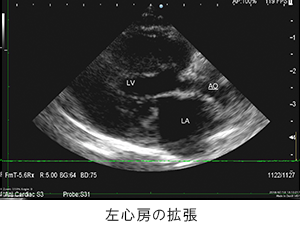

胸部レントゲン検査にて肺野の不透過性亢進像を確認。心臓超音波検査にて、心室筋の肥厚を確認。肥大型心筋症と診断。

胸部レントゲン検査にて肺野の不透過性亢進像を確認。心臓超音波検査にて、心室筋の肥厚を確認。肥大型心筋症と診断。